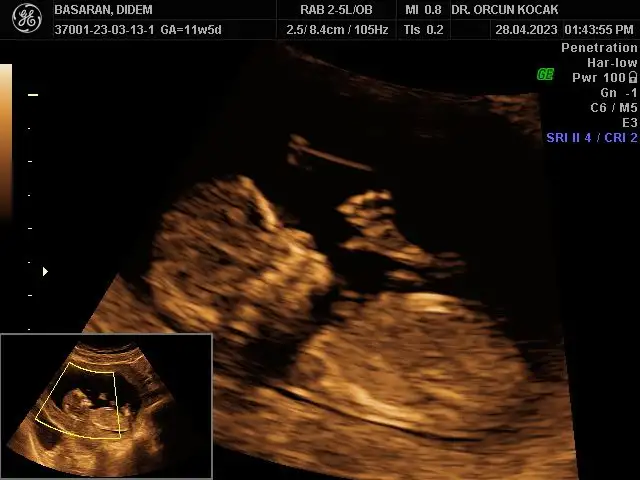

Merhabalar bende 11+5 im tahminlerinizi çok merak ediyorum kızlar sizce ne olabilirRamzi de nub’ u da erkek görünüyor canım